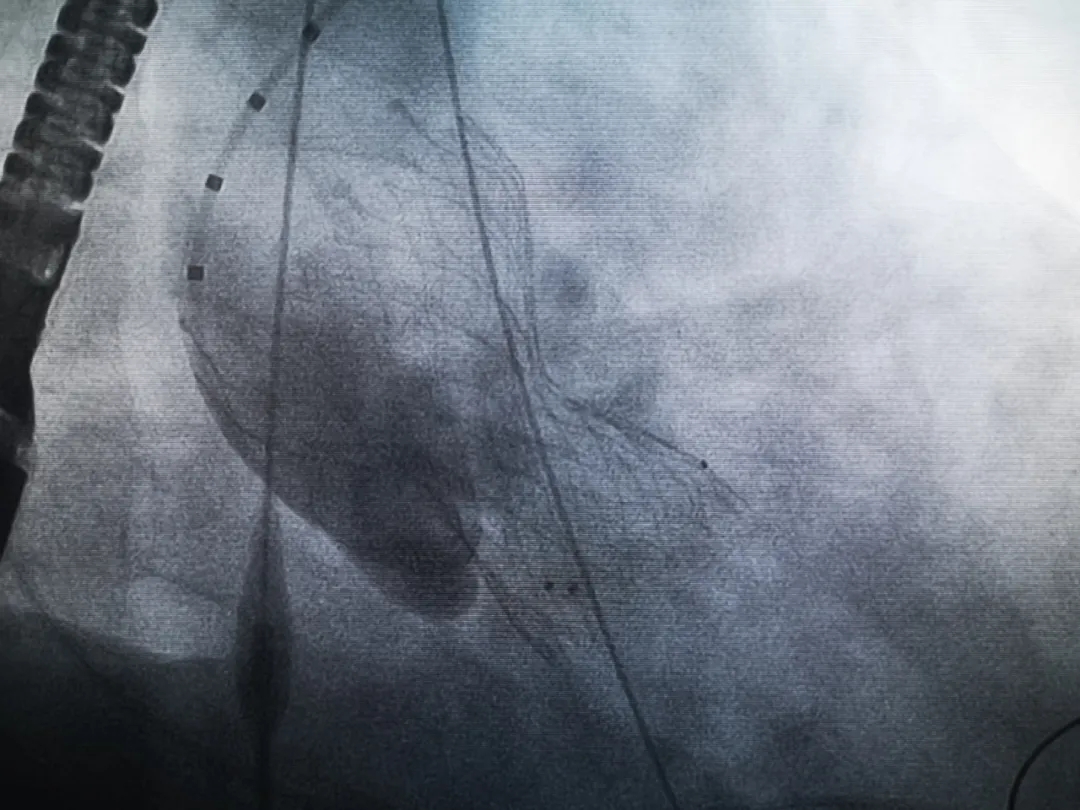

王子的手術(shù)被安排在周五。術(shù)前一天,TAVR團(tuán)隊(duì)再次碰頭討論,從麻醉中血壓控制、球囊擴(kuò)張、瓣膜釋放,到各種可能突發(fā)狀況的應(yīng)對(duì),都提前制定了方案。尤其是瓣膜鈣化極為嚴(yán)重,對(duì)于擴(kuò)張球囊型號(hào)的選擇、擴(kuò)張的力度以及瓣膜植入后瓣周漏的發(fā)生預(yù)測(cè),都具有很大挑戰(zhàn)。然而,如果沒(méi)有這些挑戰(zhàn),他又何必選擇我們呢!

手術(shù)過(guò)程緊張而有序,心臟沒(méi)有停跳,也沒(méi)有太大的血壓波動(dòng);球囊擴(kuò)張的恰到好處,瓣膜釋放之后超聲醫(yī)生的評(píng)估是至關(guān)重要的,因?yàn)槲覀兲崆熬蜏?zhǔn)備了后擴(kuò)張,也準(zhǔn)備了瓣中瓣,甚至還準(zhǔn)備了瓣周漏封堵。所幸的是,超聲診療中心劉夢(mèng)梅醫(yī)生說(shuō):沒(méi)有返流、沒(méi)有瓣周漏,瓣膜形態(tài)良好,跨瓣壓差約17mmHg(相較于術(shù)前的87mmHg還是可以接受的)。瓣膜置入的成功并不是慶祝的時(shí)候,從戰(zhàn)場(chǎng)撤退仍然需要謹(jǐn)慎。由于王子特別胖,腹股溝區(qū)脂肪尤為肥厚,在股動(dòng)脈插管拔除、確認(rèn)搏動(dòng)正常之后,便逐層縫合。同時(shí)為了美觀、縫合之后不至于鼓個(gè)包出來(lái),我們又仔細(xì)剪除了部分脂肪。術(shù)后次日,王子便可以下床活動(dòng)了。